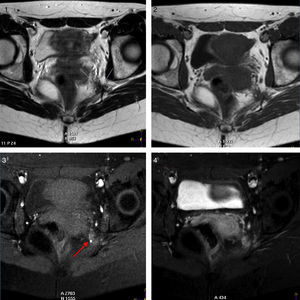

We present the case of a 30-year-old woman with no relevant history of trauma or gynaecological diseases who reported sudden-onset, recurrent pain in the perineal and left-sided internal gluteal regions. Pain was described as stabbing, tingling, and burning; the patient experienced hypersensitivity exacerbated by touch or sitting and ameliorated by standing or lying. Our patient reported no urethral or anal sphincter dysfunction or incontinence. Pain was intense and always affected the same anatomical region; it always reappeared mid-cycle and at onset of menstruation, after which it would persist, with fluctuations, for several days. The patient underwent a physical examination of the genital and perineal area and reported intense pain during a digital rectal exam, which exacerbated upon mobilisation of the cervix. Vaginal examination revealed presence of a band of fibrous tissue in the left ischial spine which was extremely painful on palpation; this structure was not detected in the contralateral area. Cutaneous examination of the left perineal area revealed hyperalgesia and positive Tinel sign; there was no clear hypoaesthesia in the area, and anal and bulbocavernosus reflexes were preserved. In light of our patient's medical history and the findings from the examination, we decided to conduct a complementary neuroimaging study to detect any endometrial lesions able to cause the symptoms reported by the patient. The gynaecological ultrasound study detected no relevant structural alterations. Our patient refused to undergo neurophysiological testing of the affected area. However, in view of her persistent clinical symptoms, she underwent a pelvic MRI scan with and without contrast during the menstrual period which revealed a haemorrhagic lesion in the lower part of the pelvic wall, at the level of the entry site of the left pudendal nerve into the Alcock canal; this finding was compatible with endometriosis (Fig. 1).

T1- and T2-weighted axial sequences (1, 2). T1-weighted fat-saturated images before and after gadolinium injection (3, 4). T2-weighted imaging displays a hypointense spiculated lesion in the pelvic floor (white arrows), in the left pelvic wall, and at the entry site of the pudendal nerve into the Alcock canal. The lesion (white arrows) shows moderate signal intensity in T1-weighted and T1-weighted fat-saturated sequences. Remnants of haemorrhage are hyperintense (red arrow in 3). Gadolinium uptake in the lesion is heterogeneous (4). Colour images are available in the electronic version of this article.